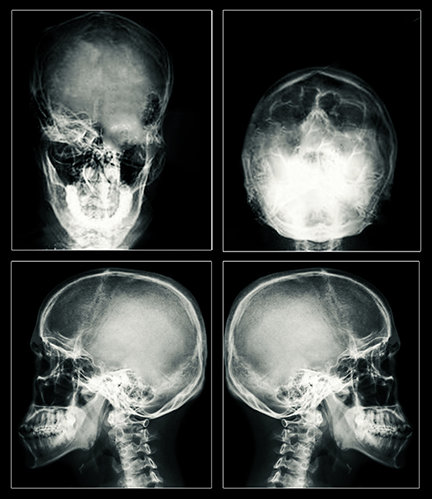

Результат остаётся прежним: большой судорожный припадок и повреждение мозга, которое может оказаться необратимым. Значительно больший ток, применяемый сегодня, может создать разрывы в клетках мозга, тем самым убивая их. Электричество также может убить клетки, нагревая их. Проведённая пациентам ЭСТ магнитно-резонансная томография (МРТ) показала: шрамы на мозге и его усыхание – неоспоримые доказательства тяжёлых повреждений.